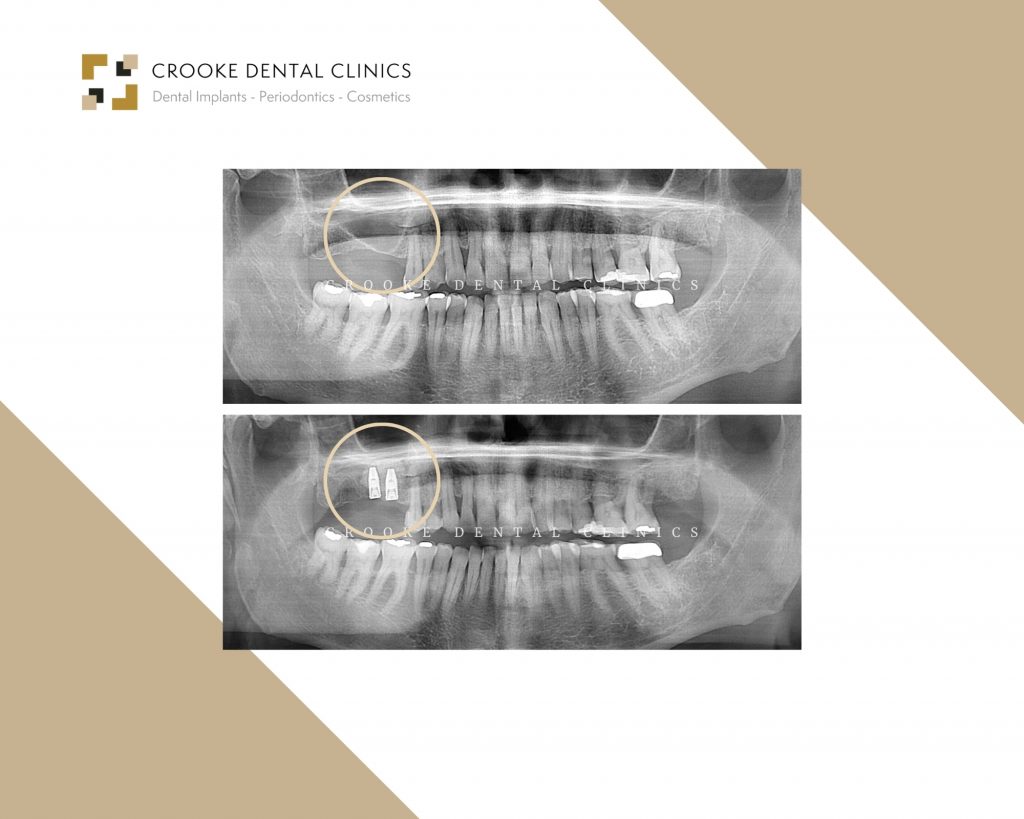

In the first quadrant, we can see patients with severe bone loss who underwent surgical sinus elevation. For this reason, we waited six months for the bone to heal and then placed two implants.